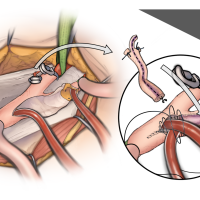

OPExPARK20220412コンテンツシリーズ

OPExPARK20220405コンテンツシリーズ

OPExPARK20220130コンテンツシリーズ

OPExPARK20220518コンテンツシリーズ

OPExPARK20220323コンテンツシリーズ

OPExPARK 2021013コンテンツシリーズ

OPExPARK 0915コンテンツシリーズ